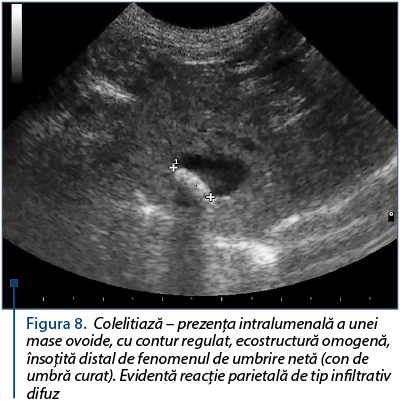

Figura 8. Colelitiază – prezenţa intralumenală a unei mase ovoide, cu contur regulat, ecostructură omogenă, însoţită distal de fenomenul de umbrire netă (con de umbră curat). Evidentă reacţie parietală de tip infiltrativ difuz

Diagnostic diferenţial se impune a se realiza faţă de mucocelul biliar (figura 7) şi litiaza biliară (figura 8). În cazul mucocelului biliar: aspect caracteristic de kiwi, vezică biliară mărită, canale biliare dilatate, la mişcarea vezicii biliare conţinutul biliar este fix; în cazul sludge-ului biliar: aspect ecografic stratificat, nu apare umbrire posterioară, apar cristale cu diametru cuprins între 2 şi 3 mm, prezintă mişcare (flow).